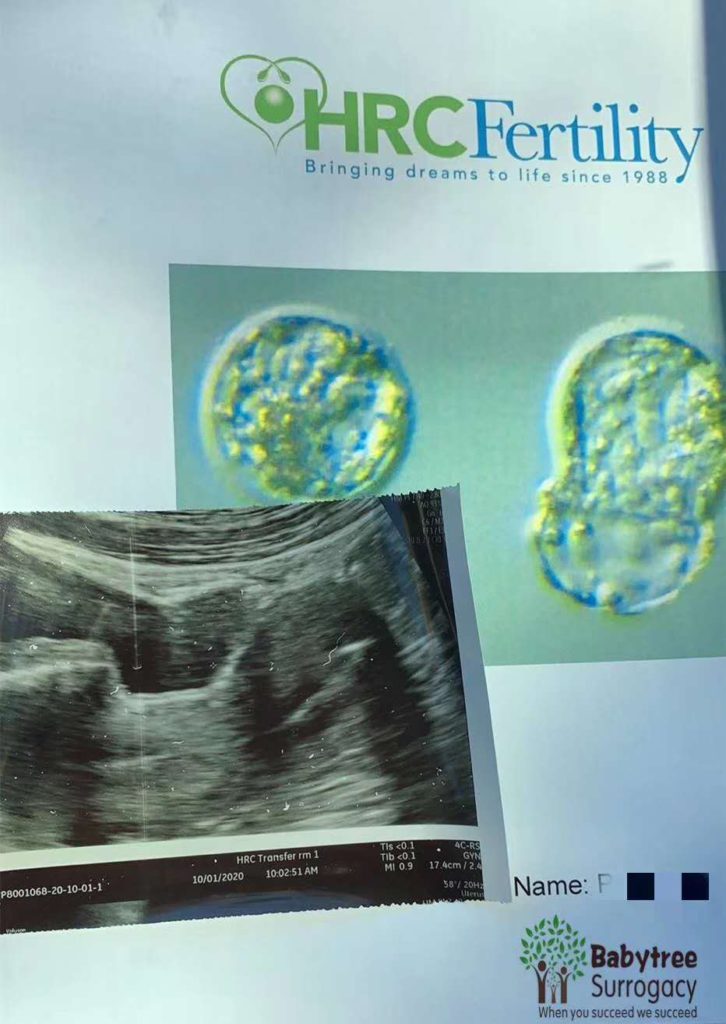

7个孕妈移植

疫情期间,移植工作也不停歇,在做好防护的基础上,我们的孕妈非常配合。

4个代孕妈妈验孕成功

在收到好孕消息后,我们第一时间和客人分享,为客人感到高兴!